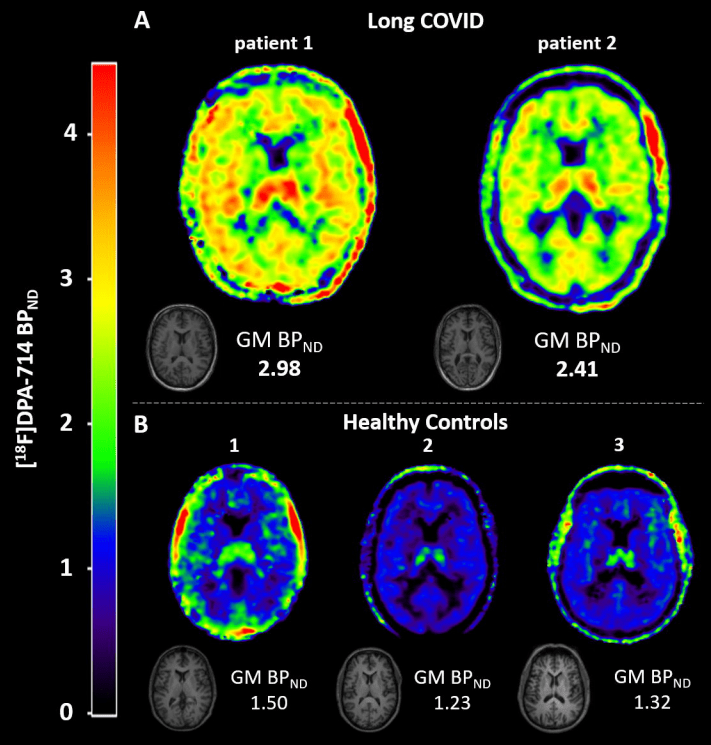

The two patients studied had a different disease course. The male patient was in the ICU and has partially returned to work. The younger female patient had mild corona complaints and is still on sick leave. In both patients, inflammation could be seen throughout the brain. The inflammations were 76 and 121 percent increased, respectively, as compared to the level seen in the brains of healthy people. These findings are important starting points for follow-up research.

Brain scans showing brain inflammation in long covid

Brain inflammation (green-yellow on the brain scan)